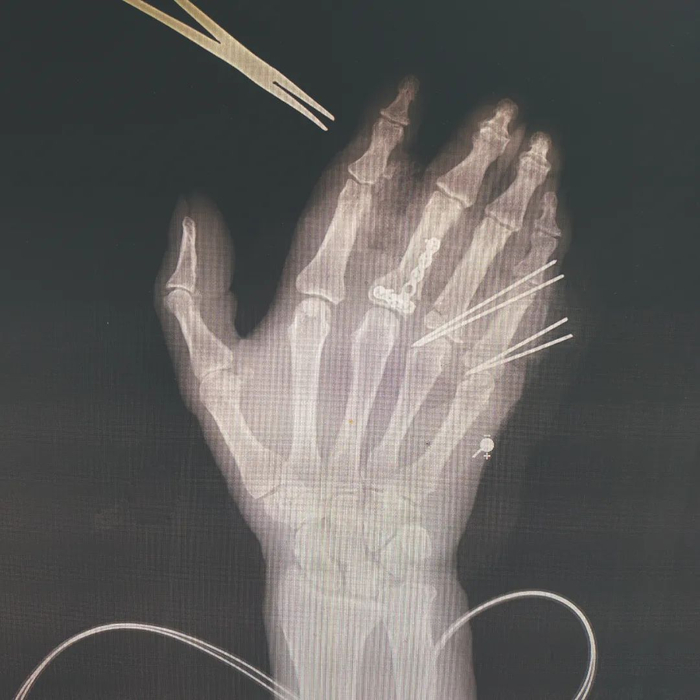

李芸右手断指再植入后图像。供图/无锡市第九人民医院

在给李芸做的手术中,钱俊先要给其清创,将铁屑等创面上的异物去除,避免造成感染,然后用克氏针(一种钢针)将李芸截断的骨骼和断指处还保有的骨骼串起来,固定回原位,这好比房子重建时要用钢筋先搭起框架。

在骨骼固定后,他将李芸被利器斩断缩回手掌的肌腱找出,再需缝合每根断指承担手指伸屈功能的两根肌腱、两根动脉、两根静脉及两根神经。血管吻合是关键。手指血管形态宛如树木伸出枝桠,指根部血管较粗,直径为1毫米,指尖部位只有0.3毫米左右。缝血管的线至少在微米级别,比头发丝还细,放在桌上根本难以看出。缝合好后,一般要观察7-10天,保证血运通畅,避免血管痉挛或者血管里形成血栓。

手外伤多为急诊,缝合一根食指大约需要两个小时,像李芸这样三根手指完全离断的再植算得上高强度工作,遇此一役,医生只能自己坚持下来,“没人替你”。见到钱俊当天,是晚上7点多,正逢他值夜班,一直到第二天早上7点前的手外伤病人都归他所在的组负责。